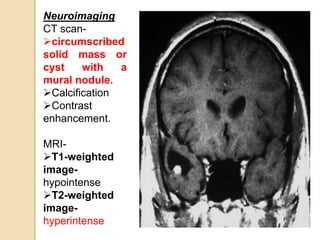

Neuroimaging

CT scan-

circumscribed

solid mass or

cyst with a

mural nodule.

Calcification

Contrast

enhancement.

MRI-

T1-weighted

image-

hypointense

T2-weighted

hyperintense